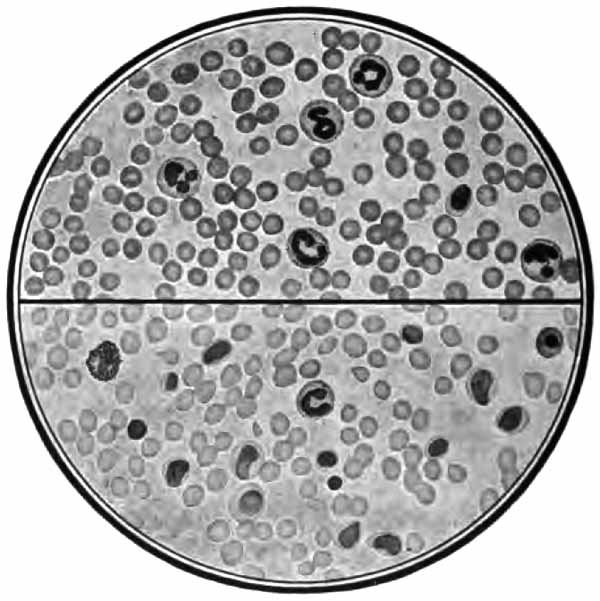

The more important structures to be seen in unstained sputum are: elastic fibers, Curschmann's spirals, [p. 27] Charcot-Leyden crystals, fibrinous casts, the ray fungus of actinomycosis, and molds. Pigmented cells, especially the so-called "heart-failure cells" (p. 43), are also best studied without staining (Plate II, Fig. 1).

In films stained by Gabbet's method tubercle bacilli, if present, will be seen as slender red rods upon a blue background of mucus and cells (Plate II, Fig. 2). They average 3 to 4 µ in length—about one-half the diameter of a red blood-corpuscle. Beginners must be warned against mistaking the edges of cells, or particles which have retained the red stain, for bacilli. The appearance of the bacilli is almost always typical, and if there seems room for doubt, the structure in question is probably not a tubercle bacillus. They may lie singly or in groups. They are very frequently bent and often have a beaded appearance. It is possible that the larger, beaded bacilli indicate a less active tuberculous process than do the smaller, uniformly stained ones. Sometimes they are present in great numbers—thousands in a field of the one-twelfth objective. Sometimes several cover-glasses must be examined to find a single bacillus. At times they are so few that none are found in stained smears, and special methods are required to detect them. The number may bear some relation to the severity of the disease, but this relation is by no means constant. The mucoid sputum from an incipient case sometimes contains great numbers, while sputum from large tuberculous cavities at times contains very few. Failure to find them is not conclusive, though their absence is much more significant when the sputum is purulent than when it is mucoid.

(1) Pus-corpuscles are present in every sputum, and at times the sputum may consist of little else. They are the polymorphonuclear leukocytes of the blood, and appear as rounded cells with several nuclei or one very irregular nucleus (Fig. 8 and Plate II, Fig. 2). They are frequently filled with granules of coal-dust and are often much degenerated. Such coal-dust-laden leukocytes are especially abundant in anthracosis, where angular black particles, both intra- and extra-cellular, are often so numerous as to color the sputum (Plate II, Fig. 2, B). Occasionally mononuclear leukocytes are present.

(c) Alveolar cells: rather large, round, or oval cells with one or two round nuclei (Fig. 13). Their source is presumably the pulmonary alveoli. Like the leukocytes, they frequently contain particles of carbon (normal lung pigment). In chronic heart disease, owing to long-continued passive congestion, they may be filled with brown granules of altered blood-pigment, and are then called "heart-failure cells" (Plate II, Fig. 1). Alveolar cells commonly contain fat-droplets and, less frequently, myelin globules. The latter are colorless, rounded bodies, sometimes resembling fat droplets, but often showing concentric or irregularly spiral markings (Fig. 13, c, g). They are also found free in the sputum. They are abundant in the scanty morning sputum of apparently healthy persons, but may be present in any mucoid sputum.

(3) Red blood-corpuscles may be present in small numbers in almost any sputum. When fairly constantly present in considerable numbers, they are suggestive of phthisis. The corpuscles when fresh are shown by any of the staining methods which include eosin. They are commonly so much degenerated as to be unrecognizable, and often only altered blood-pigment is left. Ordinarily, blood in the sputum is sufficiently recognized with the naked eye.